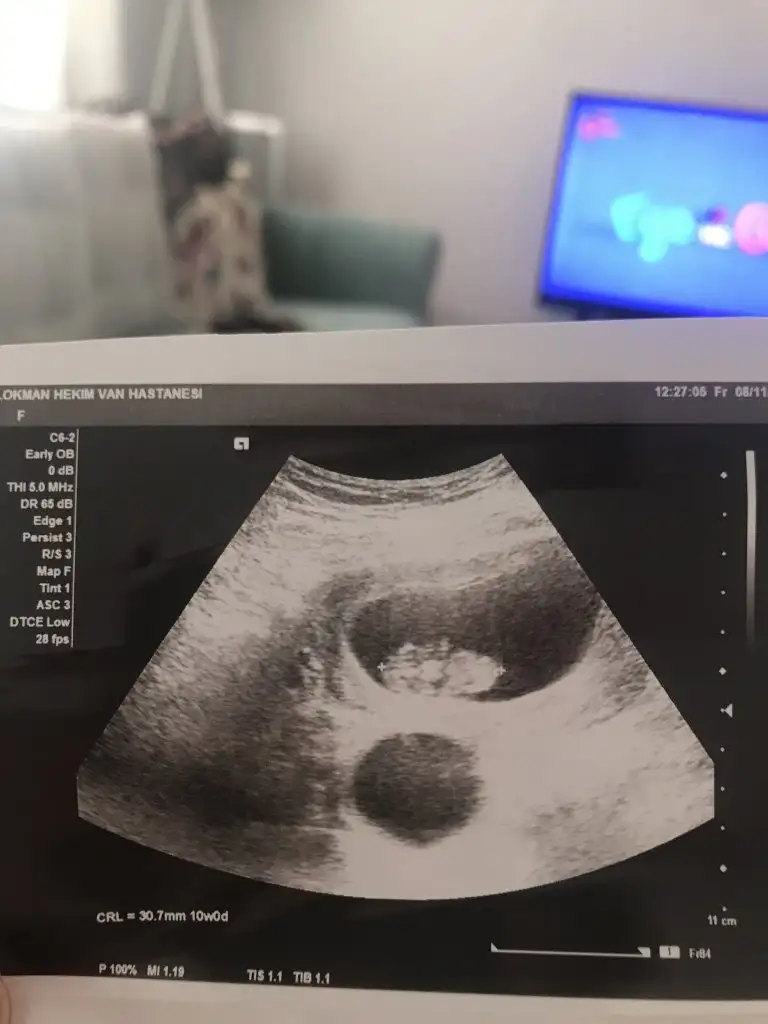

Maşallah yavru kuzuya ya. Cok sevindim canım gözün aydın darısı diger arkadaşlara. İçin rahatladı demi. Ve mükemmel bişey kalp atışı. Ben titreyerek agladım doktor dur kız oynatma karnını diyorduGunaudin canim ben de sizlere yazacaktim simdi. Ciktim doktordan Allahima binlerce sukur kalbi de duyduk bebisimi de gordum. Rabbim gormeyenlere de nasip etsin. Esim de ben de uzun boyluyuz diye diger haftalarda onden gidebilir dedi.Sukurler olsun

Gozun aydin canim cok sevindimGunaudin canim ben de sizlere yazacaktim simdi. Ciktim doktordan Allahima binlerce sukur kalbi de duyduk bebisimi de gordum. Rabbim gormeyenlere de nasip etsin. Esim de ben de uzun boyluyuz diye diger haftalarda onden gidebilir dedi.Sukurler olsun

Gozunaydın canım.devamını eylesın Rabbim saglıklaGunaudin canim ben de sizlere yazacaktim simdi. Ciktim doktordan Allahima binlerce sukur kalbi de duyduk bebisimi de gordum. Rabbim gormeyenlere de nasip etsin. Esim de ben de uzun boyluyuz diye diger haftalarda onden gidebilir dedi.Sukurler olsun

Herkese merhabalar, sat a göre 11+2

ilk geç döllenme dedi, tam bir hafta geriden geliyordu, ama sonra 1 gün ileri, sonra 2 gün geri derken her gittiğimde ölçümlerine göre değişiyor bu gün hesabı.

Kendisine bunu söylediğimde ise; bebek sonuçta dimdik durmuyor, bu yüzden yanlış da ölçüyor olabilirim endişe etme, balık gibi düşün bebeği dedi. 12 haftalık falan olduğunda daha net ölçeriz dedi boyunu.. sizin de böyle oluyor mu yoksa hep hesabınıza göre mi çıkıyor günü ultrasonda?

Aynen canım güzel gidiyor demekki bi bak bakalım yazıyor mu benim 13 mm yazıyorSağol canımBoyunu söylemedi doktor ultrason kağıdında yazar mı bakayım, valla ben de şaşırdım normalde benim hesabıma göre 9+3 olması gerekti dün gittiğimde ama doktor 10 haftalık dedi sağlıkla ilerlesin de erken geç kalması önemli değil canım